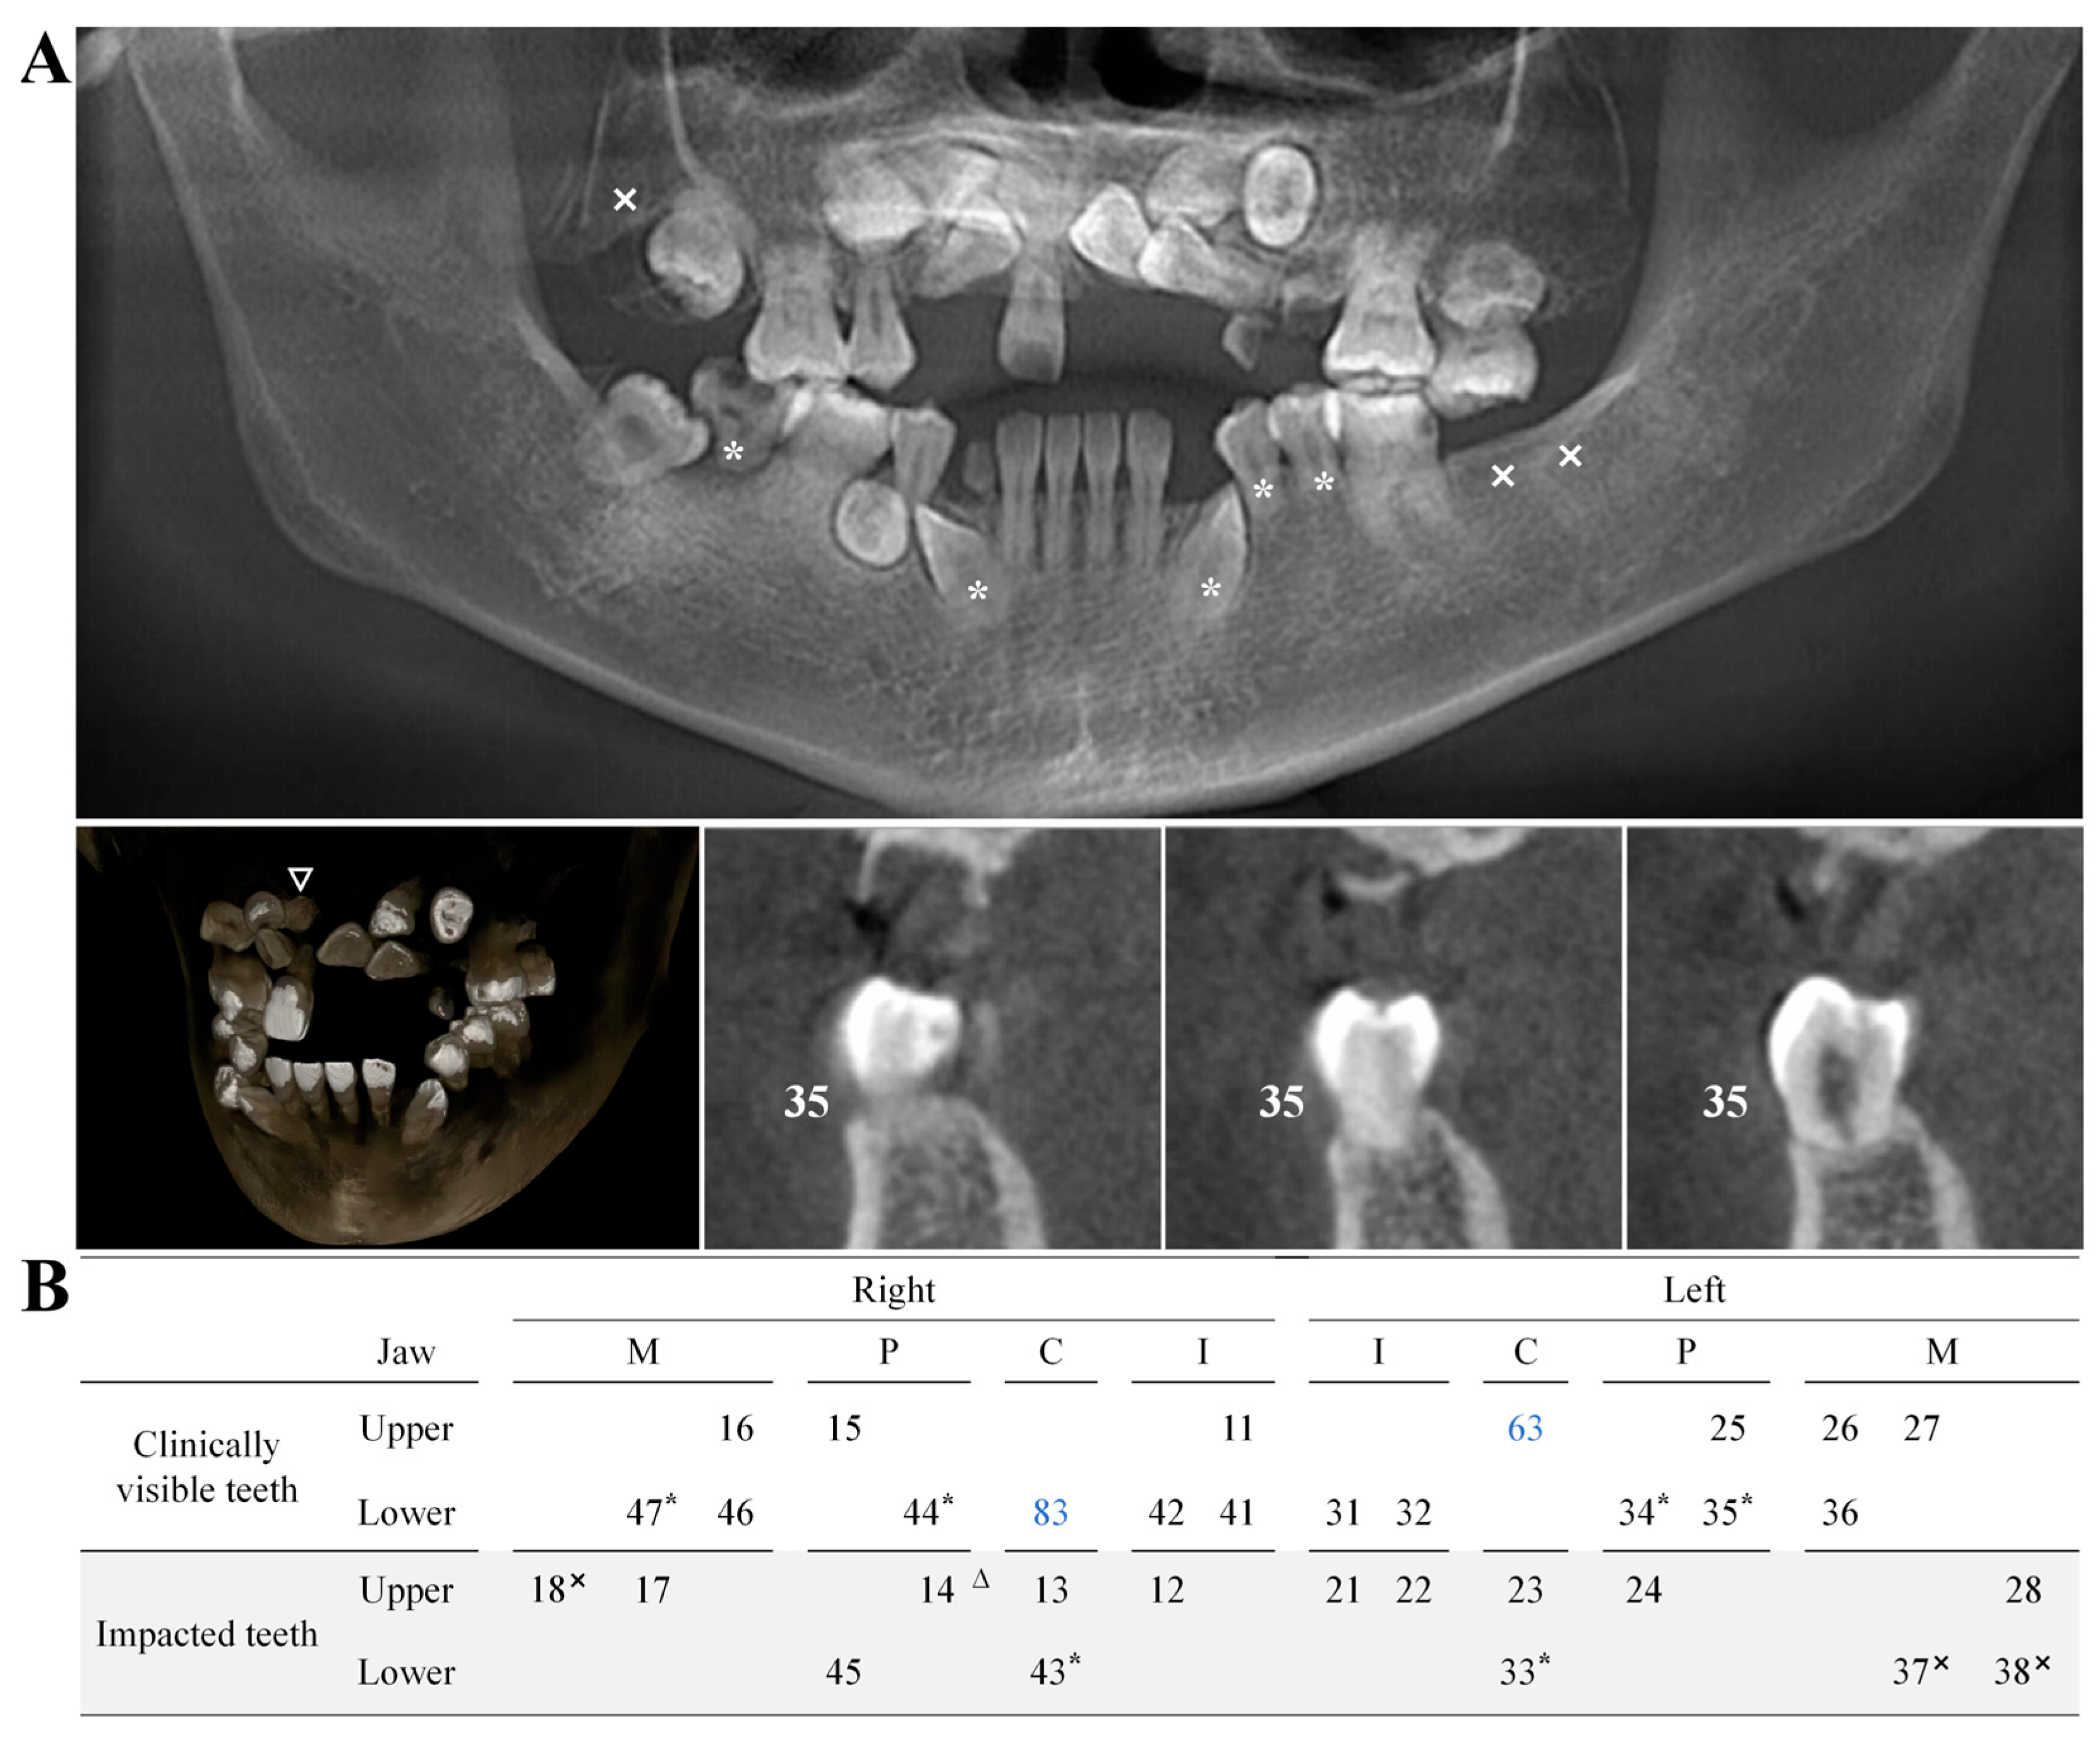

The CBCT revealed that the patient had impacted teeth, including the right maxillary lateral incisor, canine, first premolar, and second molar, as well as the left maxillary central incisor, lateral incisor, canine, and first premolar, and both the left and right mandibular canines and first premolars. Additionally, the right lower second molar was missing, and a supernumerary tooth was observed on the palatal side of the right maxillary canine and first premolar. The patient also exhibited obstructed root development in the left lower canine, first and second premolars, right lower canine, first premolar, second molar, and other teeth. No signs of trauma, root apex tumors, cysts, or other abnormalities were detected (Figure 3). The clinical significance of these findings in the context of Fahr’s syndrome lies in the impact of metabolic disturbances, particularly calcium and phosphate imbalances, on dental development. Previous studies have suggested that these metabolic disruptions, commonly seen in pseudohypoparathyroidism and other parathyroid hormone (PTH)-related conditions, can adversely affect the formation and eruption of teeth. The presence of multiple impacted teeth and a supernumerary tooth in this patient is likely a consequence of disrupted calcium homeostasis, which interferes with normal tooth development and eruption patterns.

Figure 3.

(A) CBCT imaging of the proband revealed multiple impacted teeth, with the absence of the lower right second molar (marked with “×” in the figure). Additionally, a supernumerary tooth was identified on the palatal side between the upper right canine and the first premolar (denoted by “△”). (B) Developmental anomalies were observed in the roots of the lower left canine, first and second premolars, and in the lower right canine, first premolar, and second molar (indicated by “*”). Retained deciduous teeth are marked in blue, corresponding to the upper left deciduous canine and the residual root of the lower right deciduous canine.